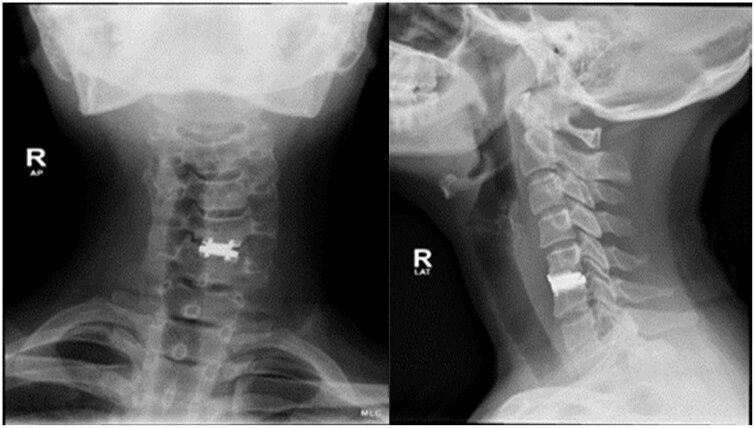

Desmoid tumours are rare benign tumours that show locally aggressive and invasive features leading to potential complications. They can be quite challenging for the treating surgeon if they occur adjacent to neurovascular structures. The aetiology of these tumours is still unclear, but the incidence is higher in females and in patients with a history of trauma or surgical procedures, raising the possibility of genetic and hormonal factors as well as post-traumatic or post-operative inflammatory changes promoting the formation of desmoid fibromatosis. We report a case of a 34-year-old Asian female who presented to our hospital with a history of difficulty in swallowing due to an enlarging lump on the left side of her neck. Patient had a past medical history of previous cervical spinal disc surgery due to a herniated disc. Diagnostic imaging showed a large soft tissue mass centred between the left common carotid artery and the cervical vertebrae displacing the trachea and oesophagus to the right side. A biopsy was obtained, and histopathological examination was suggestive of a desmoid tumour. The patient underwent surgical resection of the tumour but returned later with recurrence and had to undergo the surgery again to achieve full cure.